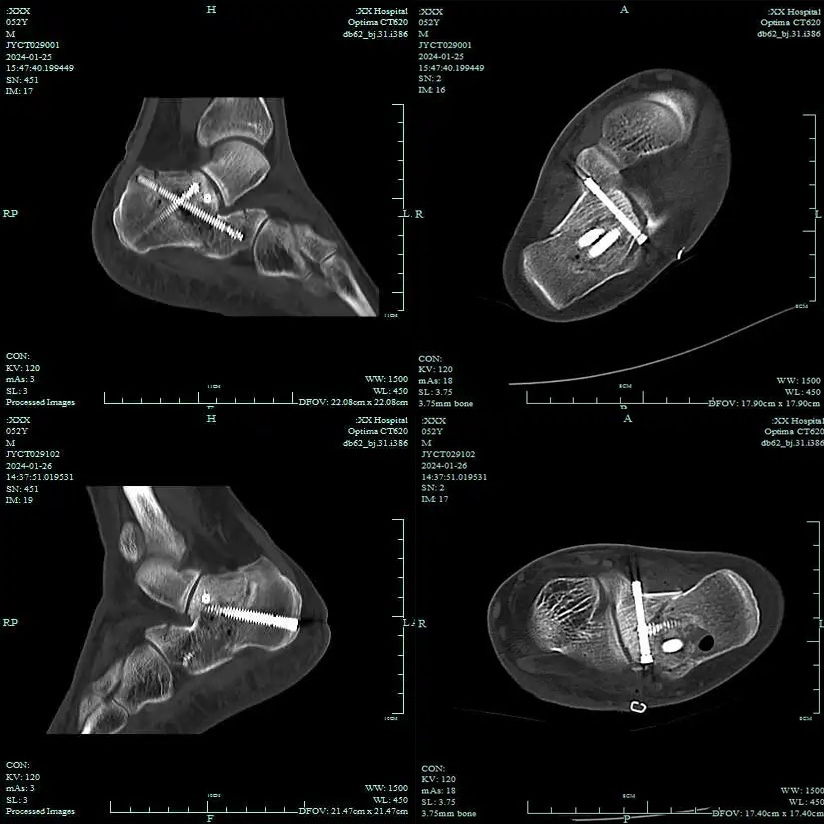

1、跟骨骨折经皮内固定术

3、跟骨骨折微创入路切开复位内固定术

经跗骨窦入路较常规L形切口入路的优势:

5、有效地降低软组织并发症,术后患者功能恢复更快。适用于SandersII型及部分简单的SandersIII型骨折。特别是Ⅱa、Ⅱb、Ⅲab型。